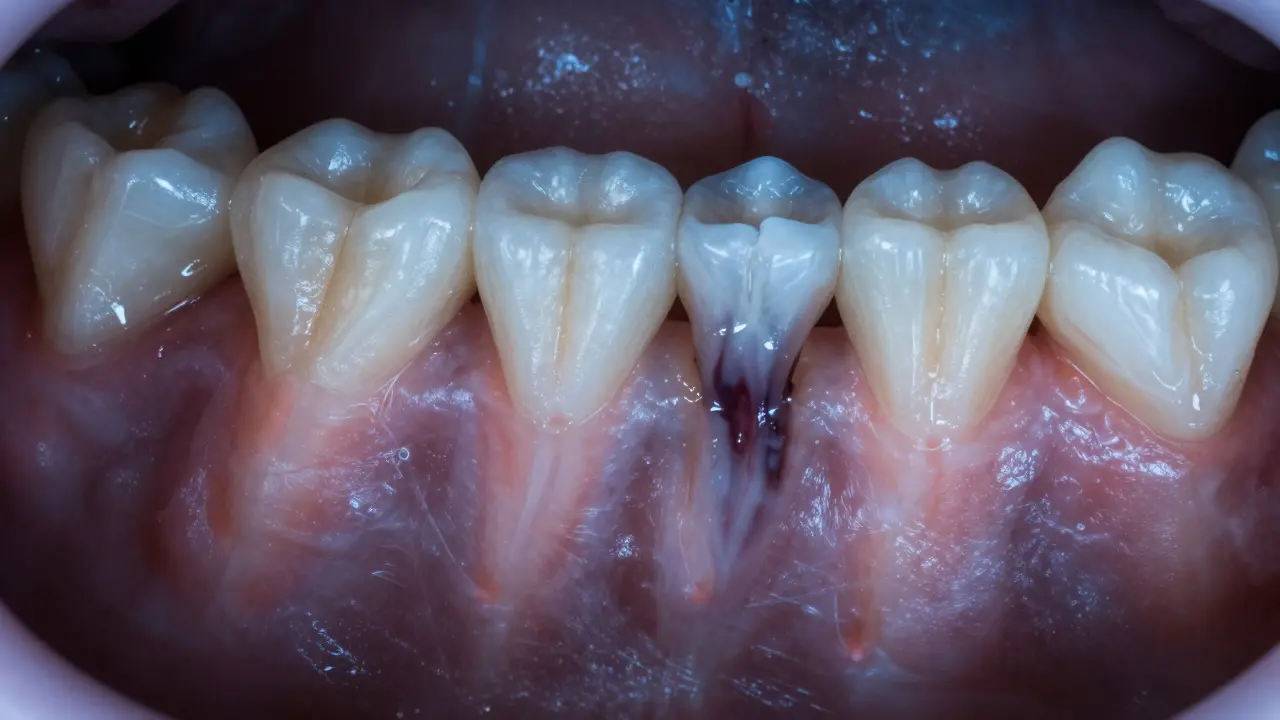

Člověk trpí bolestí zubu, pod korunkou se šíří infekce